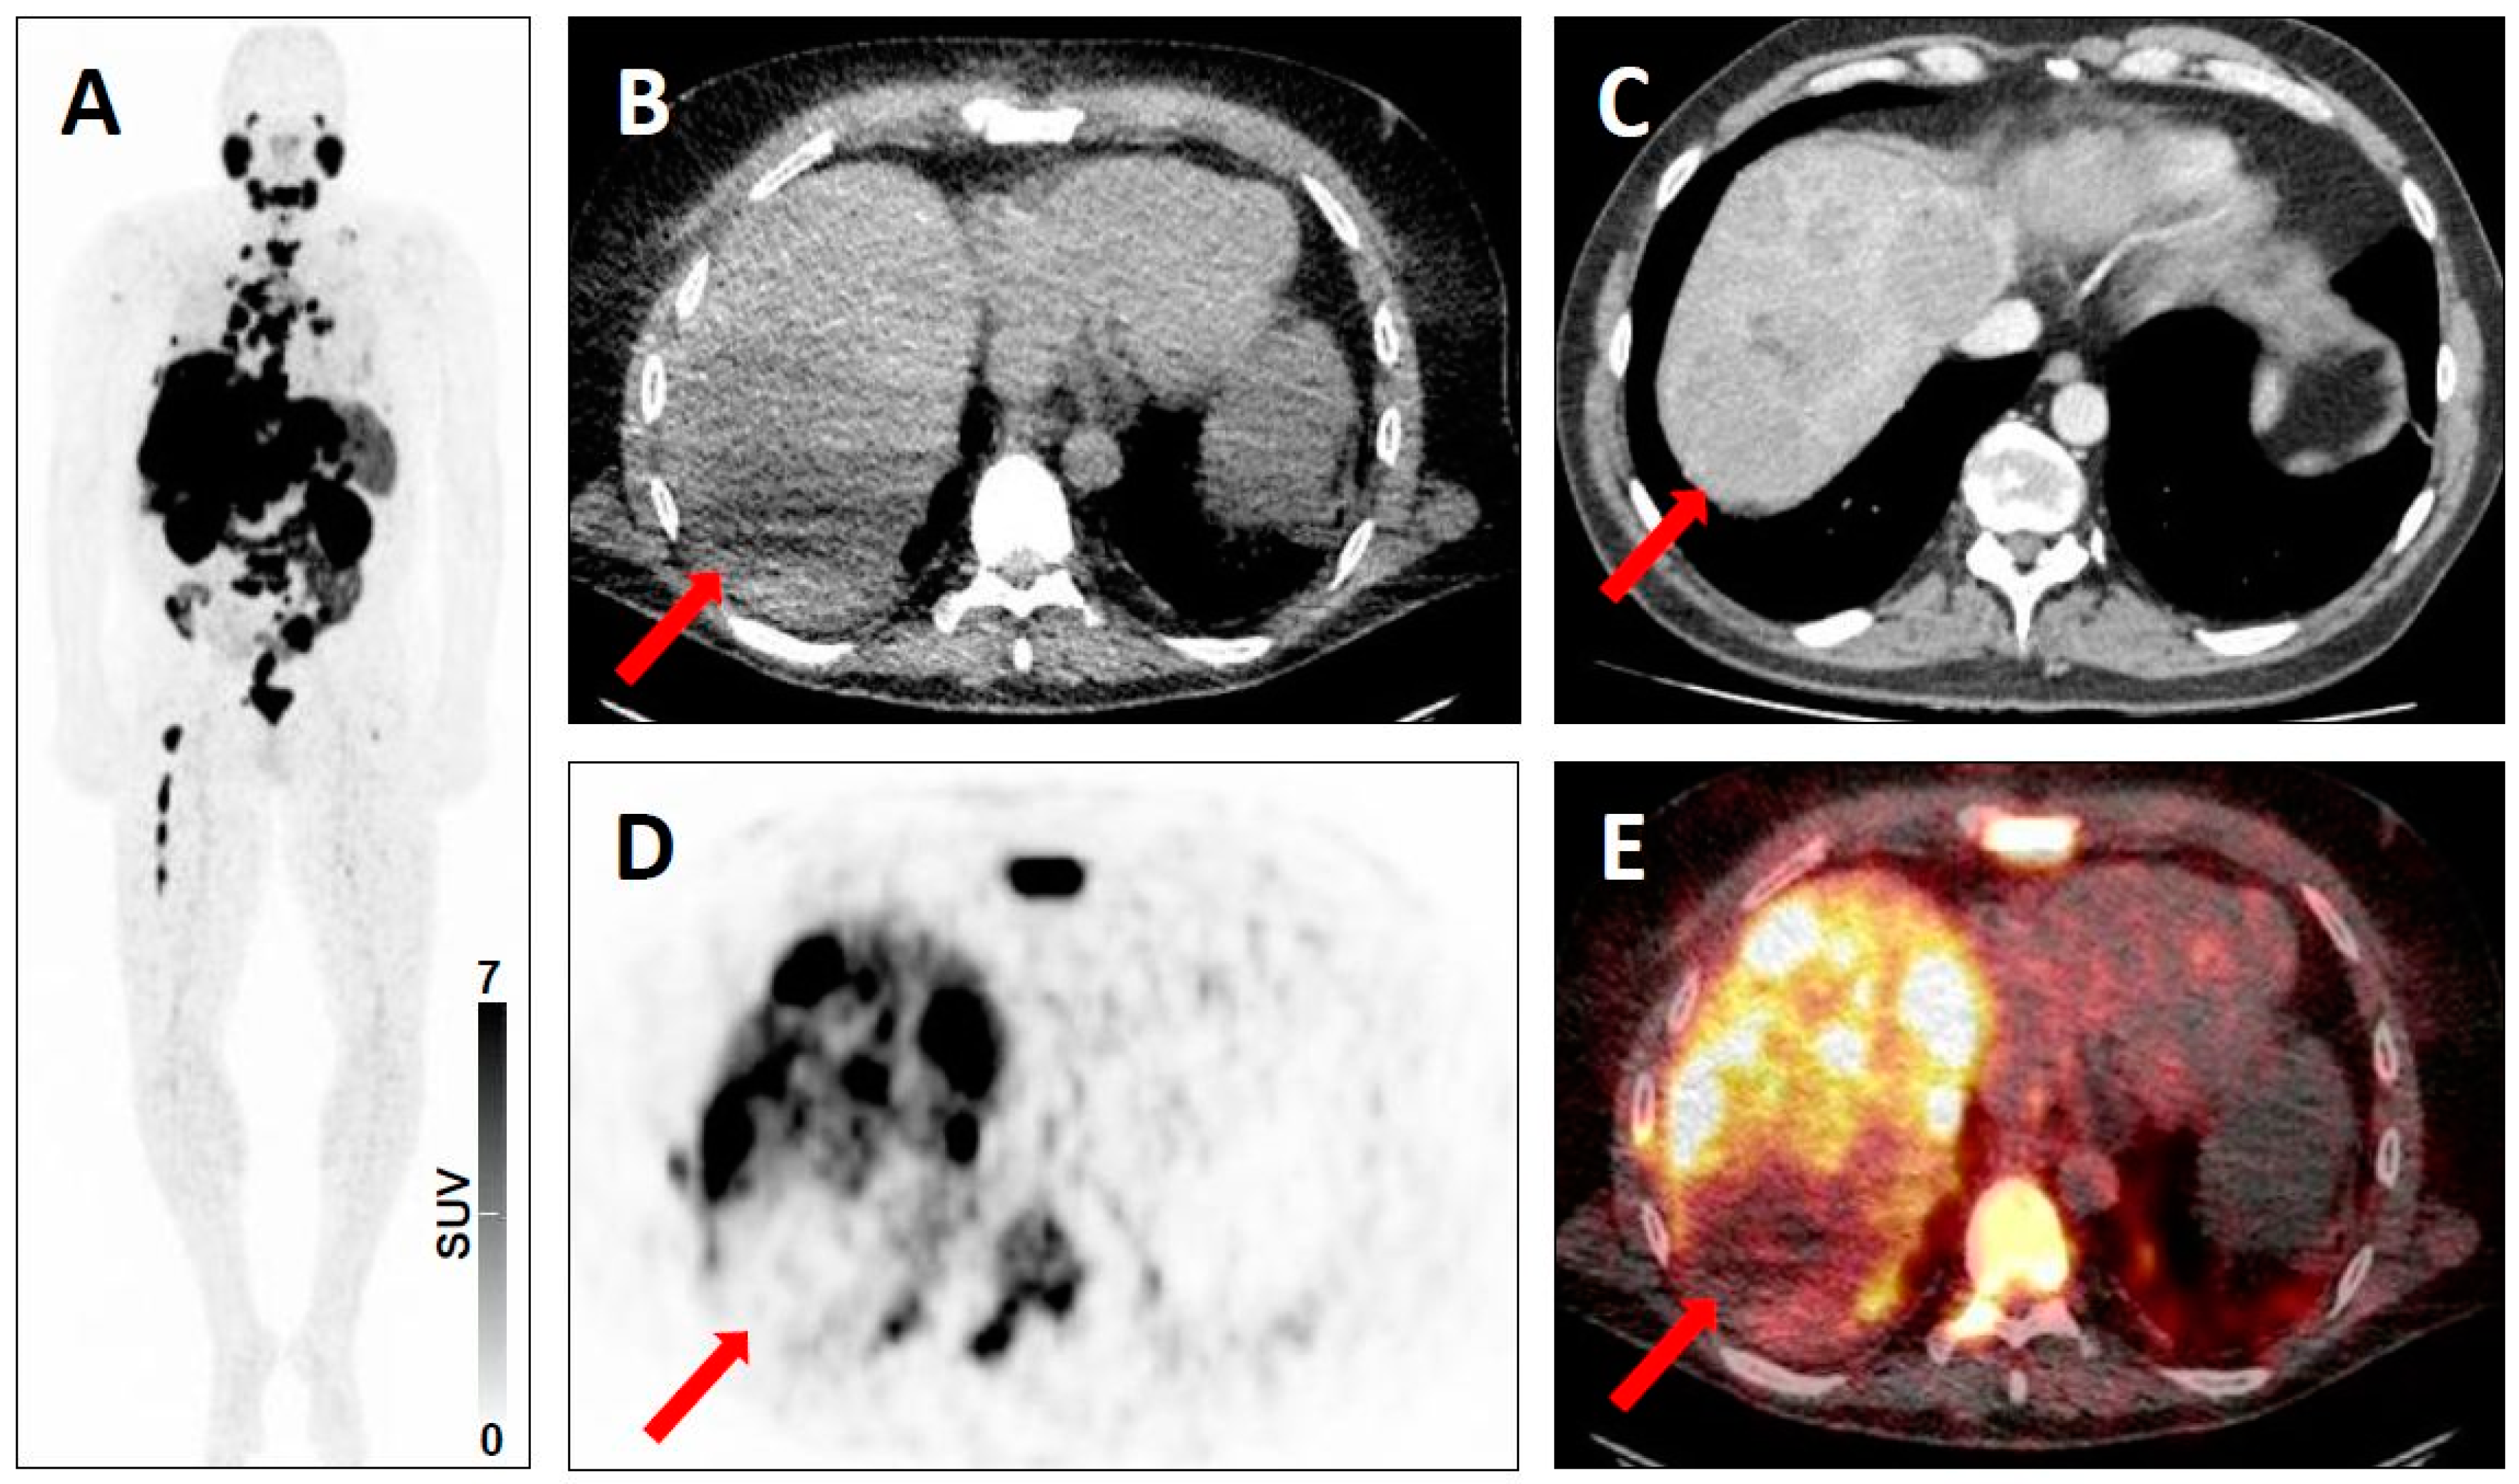

- Beauregard, J.M.; Hofman, M.S.; Kong, G.; Hicks, R.J. The tumour sink effect on the biodistribution of 68Ga-DOTA-octreotate: Implications for peptide receptor radionuclide therapy. Eur. J. Nucl. Med. Mol. Imaging 2012, 39, 50–56. [Google Scholar] [CrossRef] [PubMed]

- Werner, R.A.; Hanscheid, H.; Leal, J.P.; Javadi, M.S.; Higuchi, T.; Lodge, M.A.; Buck, A.K.; Pomper, M.G.; Lapa, C.; Rowe, S.P. Impact of tumor burden on quantitative [(68)Ga] DOTATOC biodistribution. Mol. Imaging Biol. 2018. [Google Scholar] [CrossRef]